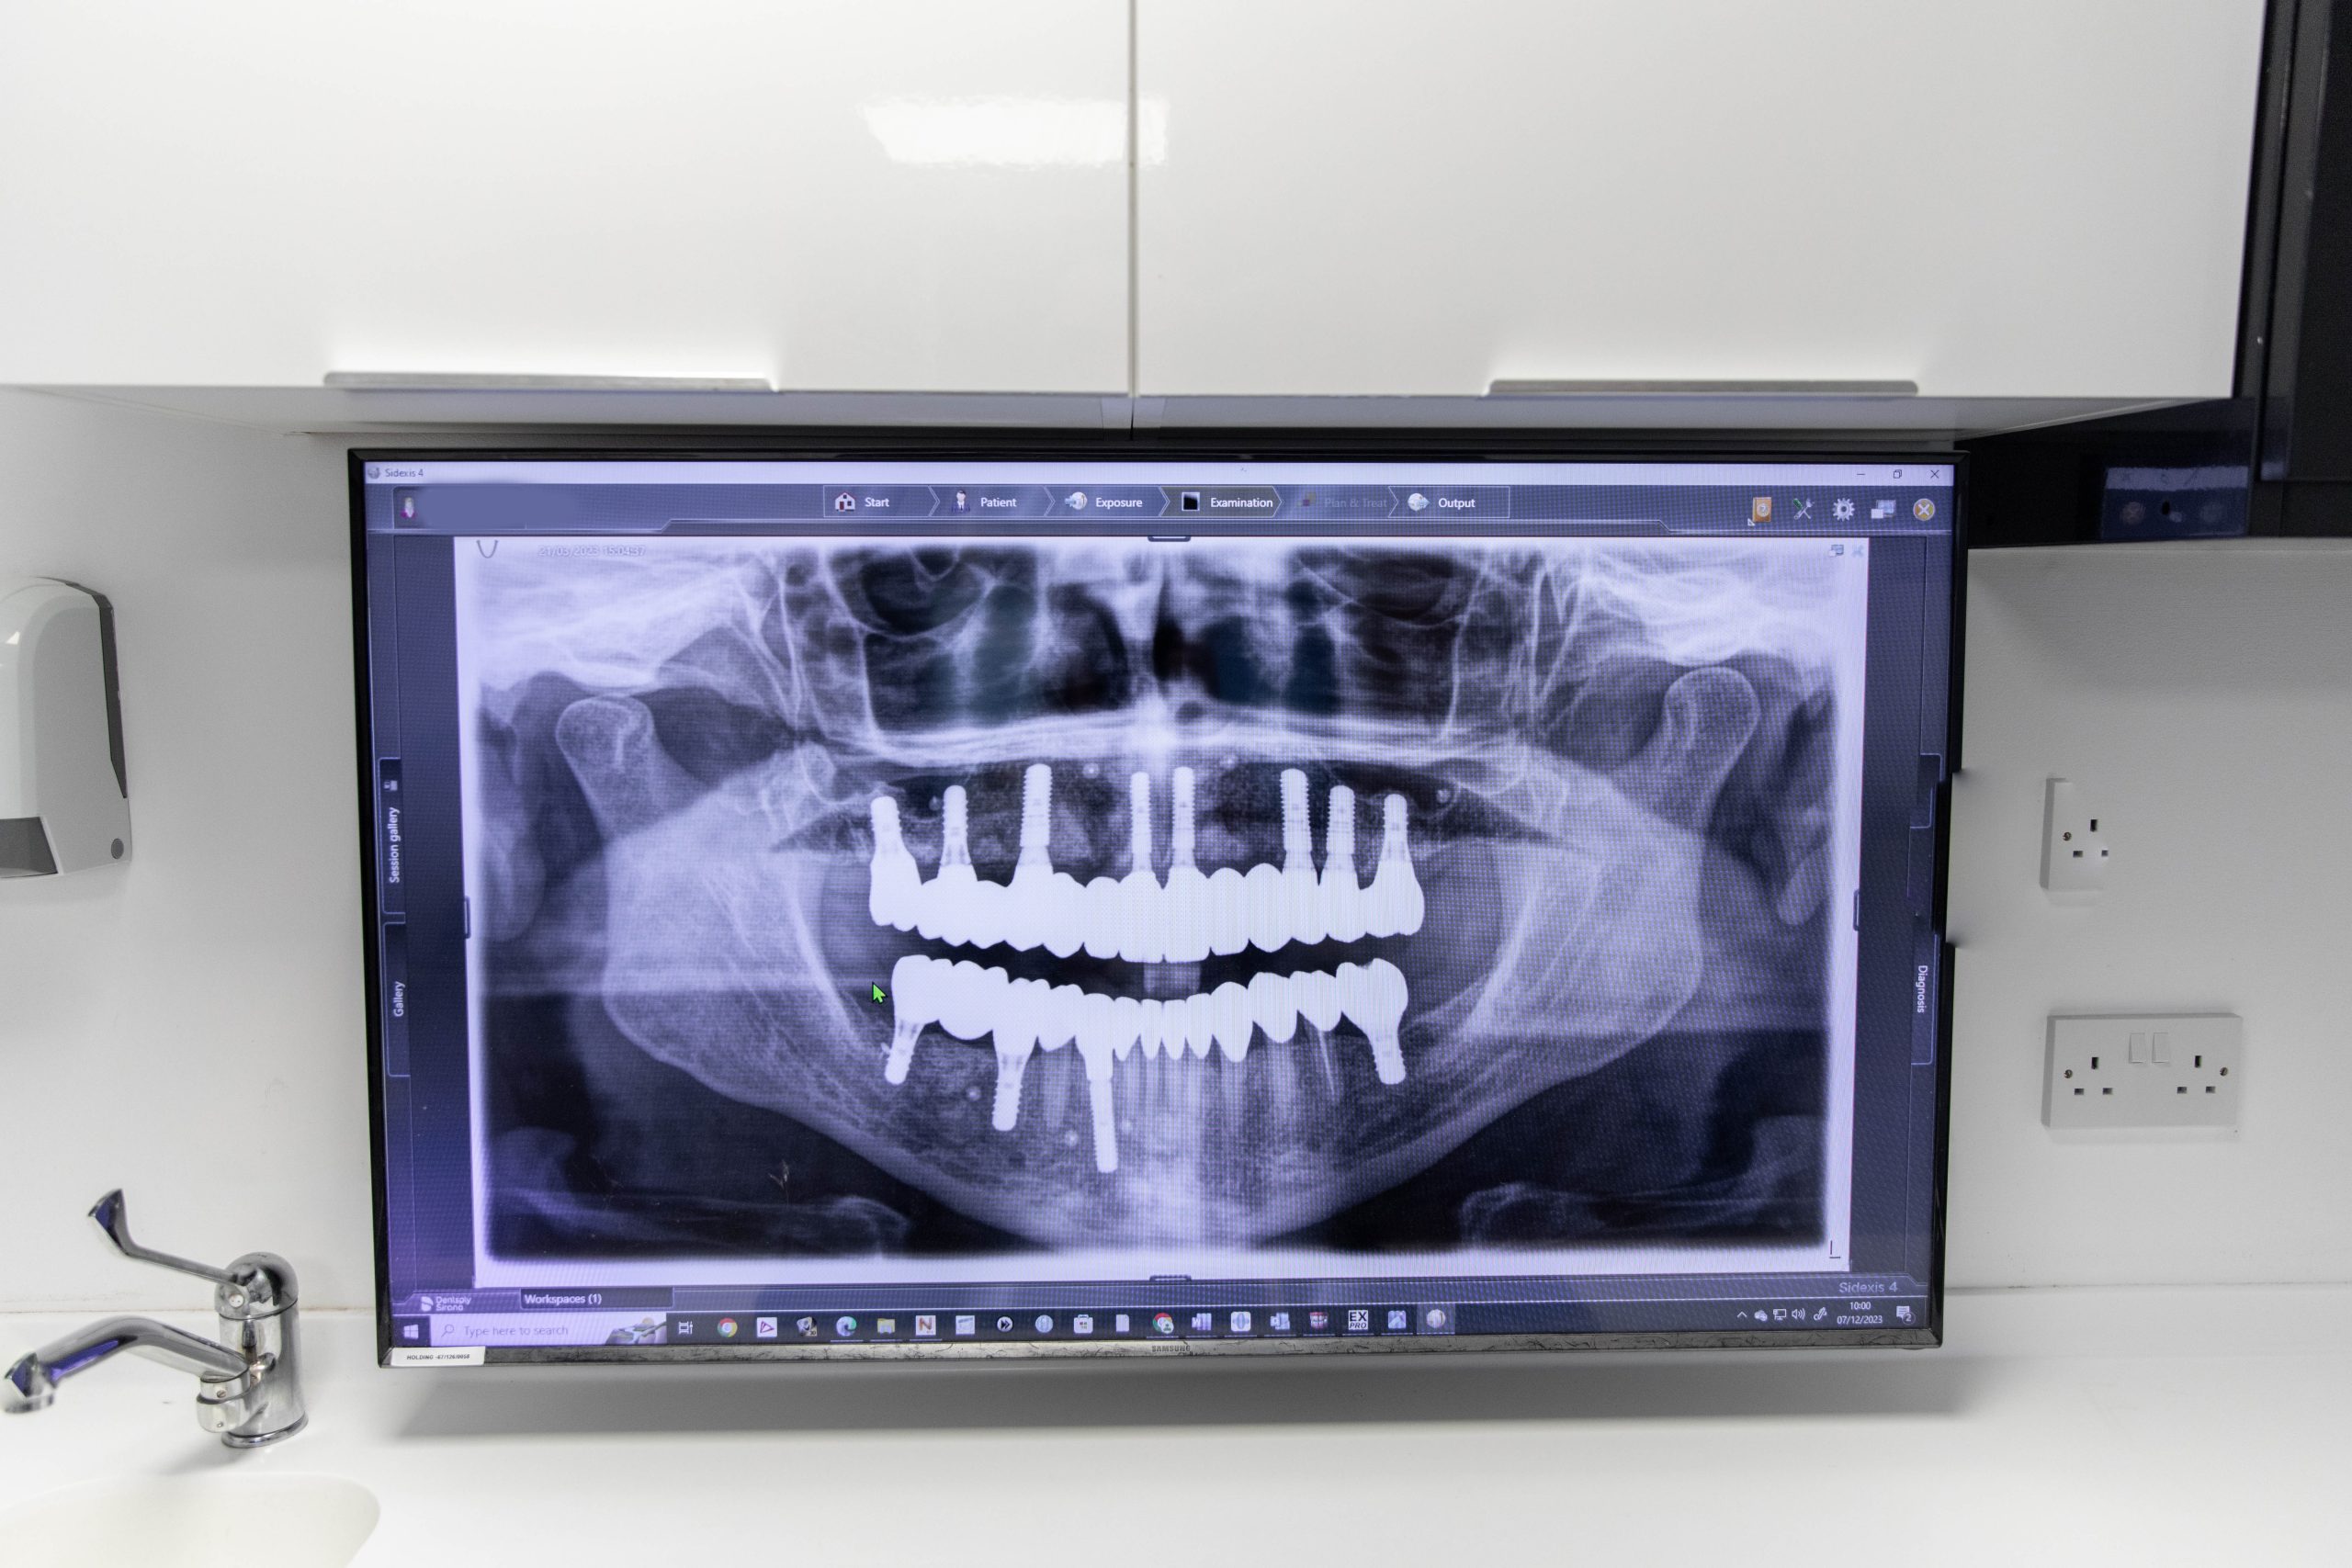

Digital radiography

Digital radiography enables us to provide highly accurate diagnosis and treatment, elevating your experience. The digital X-rays have a far superior clarity and quality, producing an exceptionally detailed image that shows even the tiniest details. Your exposure to radiation is reduced, a key consideration for many patients.

The digital X-ray is able to be viewed immediately and it can be easily repeated straight away if necessary. It can be shared with other dental professionals if required without issue.